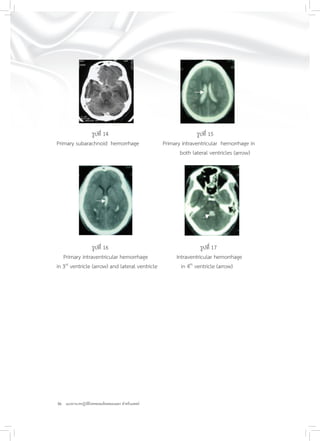

รูปที่ 14 รูปที่ 15

Primary subarachnoid hemorrhage Primary intraventricular hemorrhage in

both lateral ventricles (arrow)

รูปที่ 16 รูปที่ 17

Primary intraventricular hemorrhage Intraventricular hemorrhage

in 3rd

ventricle (arrow) and lateral ventricle in 4th

ventricle (arrow)